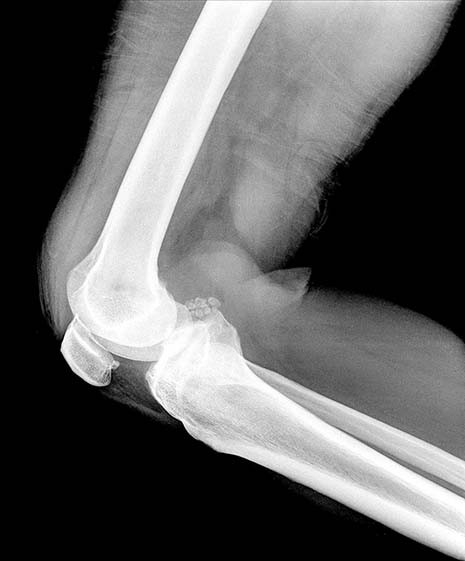

Patellofemoraal pijnsyndroom: onschuldig of niet?

Het patellofemoraal pijnsyndroom (PFPS) bestaat uit klachten op, achter en rondom de knieschijf die optreden bij traplopen, squatten, fietsen of lang stilzitten met gebogen knieën. Naast overbelasting hangen…